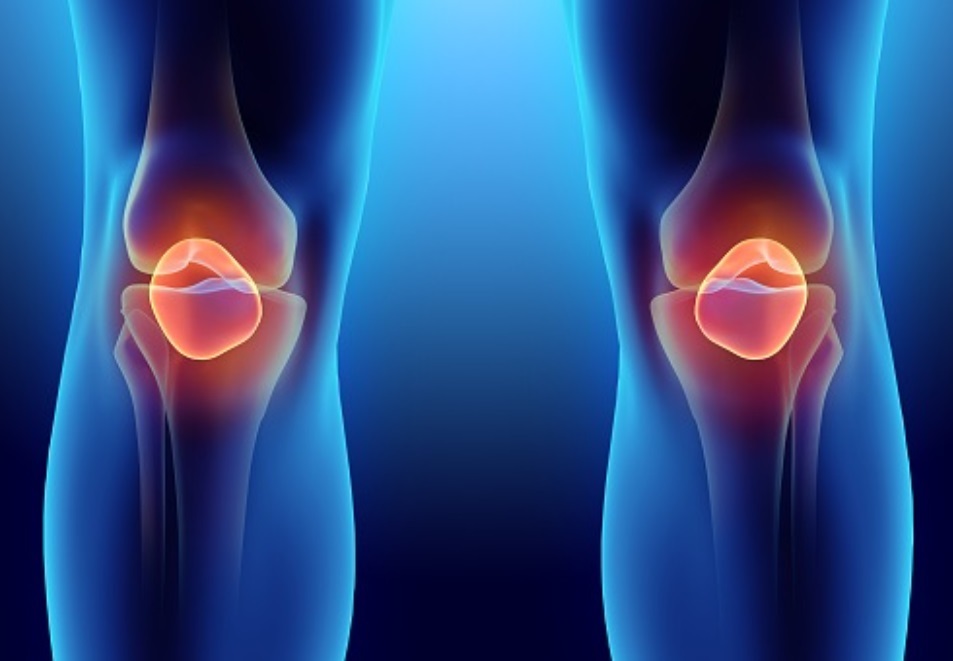

무릎관절은 한 번 손상되면 되돌릴 수 없기에 무릎관절을 보호하는 것 역시 매우 중요합니다.

무릎통증 원인 퇴행성관절염

무릎관절염은 고나절과 연골을 보호하고 있는 연골이 점차 퇴행성 병변이 생겨서 마모되고 그로 인해 뼈와 인대가 손상이 일어나서 염증과 통증을 일으키는 퇴행성 질환을 대부분을 이야기합니다.

무릎통증 원인 퇴행성관절염의 증상

무릎관절염이 발생하면 걸을 때 지속적으로 통증이 있고 무릎에 물이 차서 붓는 경우도 있으며, 심한경우에는 무릎 관절 변형이 생겨 오자다리 변형이 점점 더 심해져 절뚝거리는 걸음걸이 이상이 나타나기도합니다.

무릎통증 원인 두번째 무릎연골화증

무릎통증 원인 두번째는 무릎 관절염의 시초 무릎연골화증입니다.